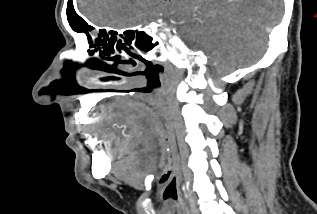

Одним из методов диагностики заболеваний носоглоточной области является мультиспиральная компьютерная томография. Методика предусматривает использование рентгеновского излучения. Благодаря различной способности тканей поглощать рентгеновские лучи и последующей цифровой обработке полученных данных, удается получить изображения исследуемой зоны в мельчайших подробностях. Рентгеновские лучи лучше всего поглощаются плотными тканями, такими как костная ткань, поэтому кости хорошо видны на снимках КТ.

При необходимости улучшения визуализации мягкотканных структур и особенно при подозрении на опухолевый процесс, применяется внутривенное болюсное контрастирование. Йодсодержащее контрастное вещество вводится пациенту в вену, после чего оно попадает в кровеносную систему и с током крови разносится по организму. Патологические очаги в большей степени накапливают контраст, что на снимках придает им детальность и яркие очертания на фоне окружающих здоровых тканей.

Инновационные цифровые приложения томографов позволяют получить снимки высокого качества и детализации, а также создать трехмерные реконструкции анатомической зоны исследования, что дает возможность рассмотреть пространственное расположение органов и патологических образований. КТ носоглотки с контрастом назначают при подозрении на рост новообразований, в случае хронического воспаления, при врожденных аномалиях строения носа и прилегающих к нему придаточных пазух.